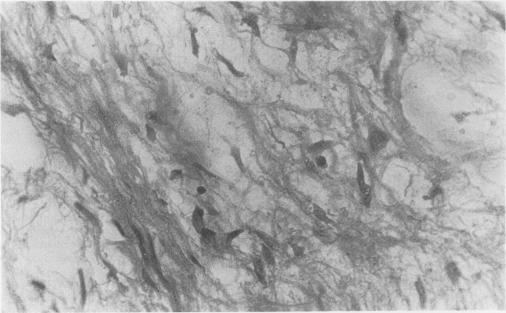

A 23-year-old Nigerian man with a giant (8.5 kg) benign intrathoracic fibromyxoma presented in respiratory distress with what looked clinically and radiologically like a massive left-sided pleural effusion. The correct preoperative diagnosis was suggested by an almost 'dry tap' together with a solid resistance to the aspiring needle at chest aspiration. Complete removal was successfully accomplished through an extended left thoracotomy. The pathology, clinical features, and treatment of localised pleural fibromas are briefly discussed.

一名23岁的尼日利亚男子患有巨大(8.5千克)的良性胸内纤维黏液瘤,因呼吸窘迫就诊,临床和放射学表现均类似大量左侧胸腔积液。胸腔穿刺时几乎“干抽”且穿刺针遇到坚实阻力,提示了正确的术前诊断。通过扩大的左胸切开术成功实现了完整切除。本文简要讨论了局限性胸膜纤维瘤的病理、临床特征及治疗。